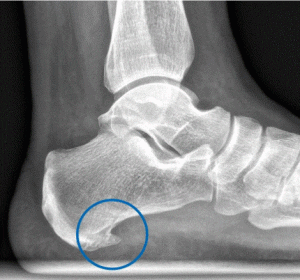

Con el paso del tiempo, los tejidos pierden elasticidad y capacidad de adaptación. Esto puede derivar en sobrecargas compensatorias en el talón, favoreciendo la aparición de espolones. No es raro encontrar personas mayores con formaciones óseas visibles en radiografías, aunque no siempre sean dolorosas.

No siempre. Muchas personas tienen espolones visibles sin dolor, mientras que otras tienen dolor sin presencia radiológica de espolón. Lo importante es identificar si la estructura está en fase inflamatoria o si es una secuela anatómica de una sobrecarga.